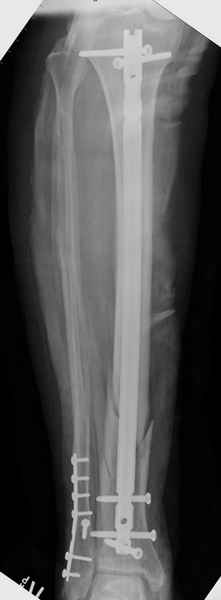

Здесь мы использовали новый Synthes Nail с дополнительными дырками, в проксимальной части 4: по две косых и поперечные (один стандартный а другой динамический), в дистальной части две поперечные, прямая и косая. Вес больного более 120 кг, нагрузку начнем через месяц.

Получилось красиво, поздравляю. Вверху можно было ограничиться одним винтом во фронтальное статическое отверстие, зачем два 45-градусных?

При такий спирали задний край tibia может быть сломан - нет ли этого в данном случае? На всякий случай можно было ввести 1-2 винта 4,5 мм спереди назад мимо гвоздя. Хотя самый дистальный блокирующий винт, возможно, зацепил этот отломок. А какой тут диаметр гвоздя и locking винтов?

Если там и правда сломан задний край, то лучше с нагрузкой подождать, даже будь больной полегче.